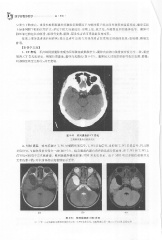

Page 342 - 医学影像诊断学